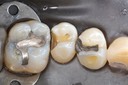

Kyle Chock #18 prep